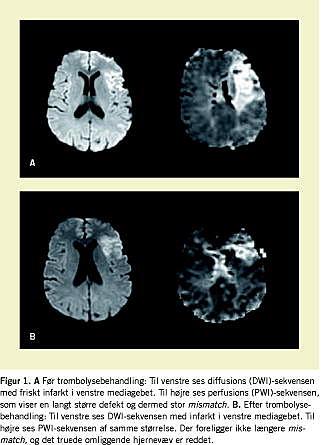

De primære visitationskriterier for at modtage apopleksipatienter til vurdering med henblik på trombolysebehandling er simple. Der skal være tegn på akut apopleksi inden for tre timer, hemiparese, ansigtsskævhed og tale- eller synsforstyrrelser. Behandlingen er registreret til patienter på 18-80 år, og patienten skal være tidligere selvhjulpen. Er starttidspunktet usikkert, f.eks. hvis patienten vågner op med symptomer, må starten dateres tilbage til tidspunktet, hvor patienten sidst var set rask. Behandlingen forudsætter, at man ved computertomografi (CT) eller magnetisk resonans (MR)-skanning har udelukket intrakranial hæmoragi. I de tilgrundliggende randomiserede kliniske undersøgelser blev der brugt CT ved inklusion. MR-skanning giver mulighed for at vurdere, om der er væv i randzonen (den iskæmiske penumbra), som kan reddes (Figur 1 ). Ifald vævet allerede er dødt, kan behandlingen ikke gavne, og man kan så afstå og derved undgå at påføre patienten en blødningsrisiko. Især hos patienter med udtalte neurologiske udfald eller med symptomer i remission giver MR-undersøgelsen vigtige yderligere oplysninger.

Siden godkendelsen af rt-PA i USA i 1996 har trombolysebehandling været givet efter den oprindelige NINDS-protokol på basis af CT af cerebrum og inden for de første tre timer efter start. Studiet tog ikke højde for typen af infarkt (storkars- eller småkarsinfarkt, emboli, dissektion m.m.), om der var karokklusion, og om der var risiko for, at infarktet ville tiltage i størrelse (iskæmisk penumbra). Protokollen er ikke revideret siden, men diagnostikken har udviklet sig markant i den sidste dekade. CT kan suppleres med perfusions- og angiosekvens og med ultralyd af de præ- og intracerebrale kar. Især MR-skanning med diffusions- (DWI), perfusions- (PWI) og angiosekvens giver yderligere oplysninger, som giver bedre selektion af patienterne til optimering af trombolyseeffekten og samtidig en mindskning af risikoen for bivirkninger. Adskillige ny trombolytiske præparater med formodet bedre risiko-effekt-profil afprøves for tiden. I fase II-studier med Desmoteplase er trombolyse op til ni timer efter symptomdebut [8, 9] med varierende succes blevet afprøvet hos selekterede patienter med påvist perfusion-diffusions-mismatch. Om tidsvinduet kan udvides, er endnu usikkert.